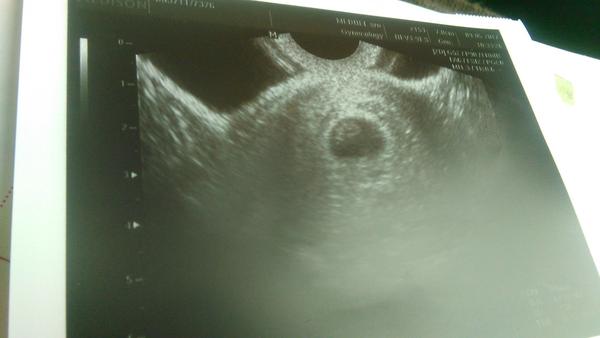

Termín pôrodu apríl 2017

Ahojte baby, su tu uz nejake, co maju termin v aprili 2017? Boli ste uz na prehliadke u svojho gyn? Mna objednal doktor na prvu prehliadku az v 8TT tak som nervozna ako prehliadka dopadne. Povedal, ze nema zmysel chodit skor, ze aj tak by nic nevidel 😒